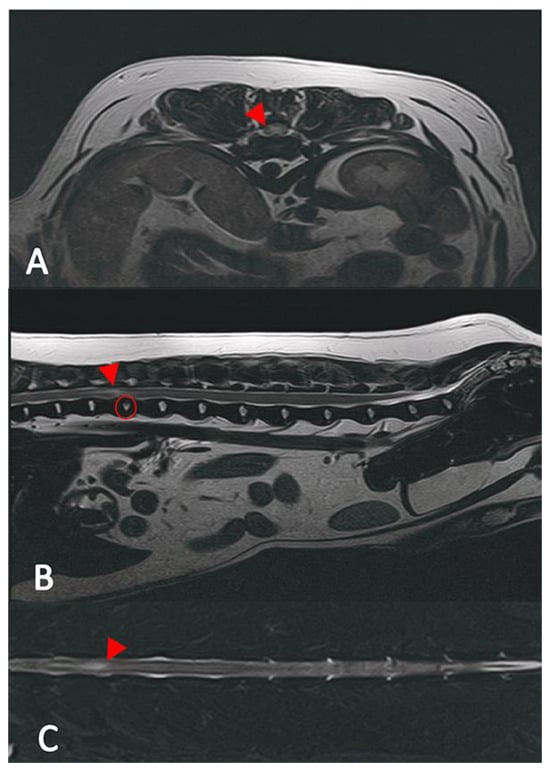

2.2. Diagnostic Imaging (CT and MRI)

2.3. Image Analysis